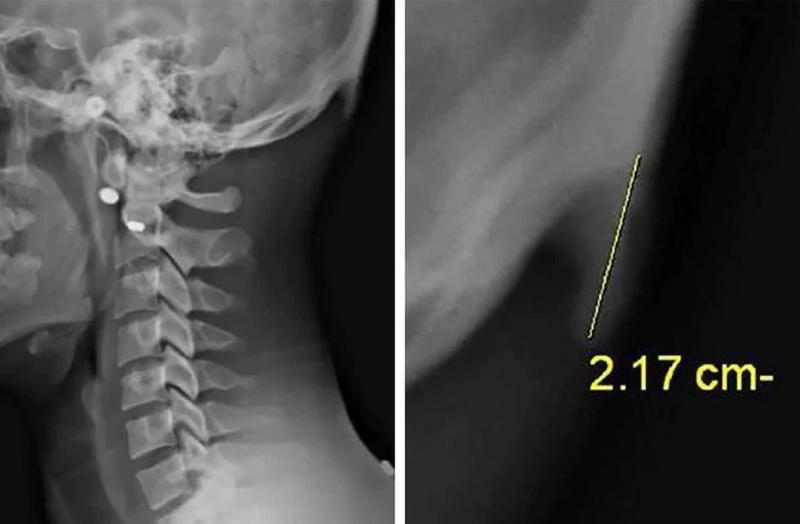

Zo'n 41% van de 18- tot 30-jarigen heeft achteraan zijn hoofd een botachtige bult van 10 tot 30 millimeter zitten. Dat blijkt uit de analyse van 218 röntgenfoto's van jongeren uit de buurt van Brisbane door twee onderzoekers van de University of the Sunshine Coast. De uitstulpingen zijn het gevolg van langdurige druk op de botten in de buurt van de bult en typisch voor oude mensen met een slechte lichaamshouding. Maar door ons smartphonegebruik komt het nu ook bij jonge mensen voor.

Veel groter dan normaal

"Door je hoofd naar voren te buigen, verschuift het gewicht van je hoofd van je nekwervels naar de spieren aan de achterkant van je hoofd en nek", legt dokter David Shahar uit aan NZ Herald. "Het is belangrijk te beseffen dat zo'n uitstulpingen meestal maar een paar millimeter groot zijn, maar bij deze jongeren vonden we gevallen tot 30 millimeter groot. Dit is een bewijs dat de aftakeling van ons spier- en botstelsel al op een vroege leeftijd kan beginnen."